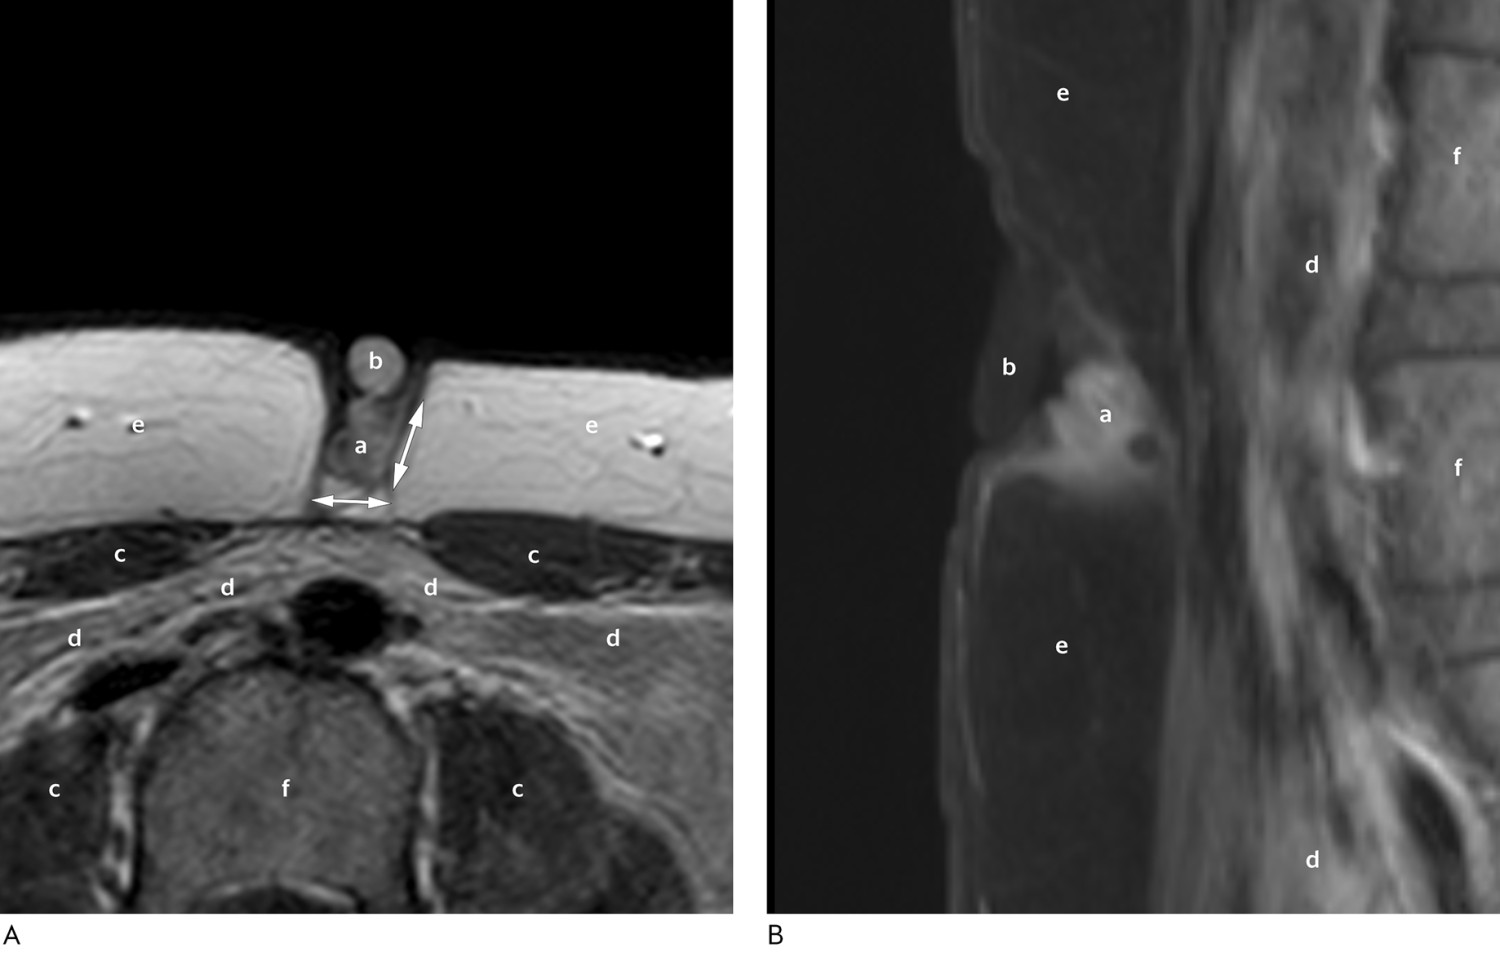

Ultralyd viste polypøse lesjoner som smeltet sammen i dypet av navlen, tolket som mulig endometriose eller urachusfistel. Det ble anbefalt videre utredning med magnetisk resonanstomografi (MR). Ni uker etter konsultasjonen ble MR-undersøkelsen gjennomført med standard bløtvevstumorprotokoll. Denne viste en velavgrenset lesjon 1 cm i diameter i fettvevet ekstraabdominalt ved umbilicus med kontrastoppladning av usikker etiologi, forenlig med endometriose eller granulom (figur 2). Sarkom ble vurdert som mindre sannsynlig, men det ble anbefalt henvisning til sarkomgruppen ved universitetssykehus. Her ble det tatt finnålsaspirasjon, som var forenlig med endometriose. Kvinnen ble henvist videre til lokalsykehusets kvinneklinikk. Klinisk undersøkelse her viste en 7 mm stor rund oppfylling superfisielt i navlen og to mindre oppfyllinger proksimalt for denne. Området varierte mellom hudfarge og rødlig farge, og oppfyllingene var myke ved palpasjon. Transvaginal ultralyd viste en upåfallende uterus og normale ovarier bilateralt. Indre genitalia, blære og tarm var fritt mobile og uømme.